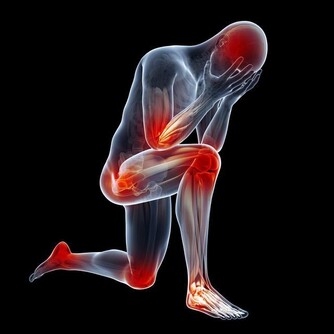

*****1、 腰痛:*****

引起腰部疼痛的原因有很多,但是醫生診斷的時候都會首先考慮腎臟疾病引起的腰痛問題,因為腎陽不足很容易導致腰部的疼痛。西醫方面認為,腎臟的疾病和風濕病、腰肌勞損等症狀都會引起腰部的疼痛。所以,腰疼可能是腎虛。

*****5、 畏寒肢冷:*****

畏寒怕冷是腎陽虛的表現之一,腎虛就會陽氣不足。陽氣可以保證身體的溫熱,腎虛導致陽氣不足那麼抗寒能力就會降低,畏寒怕冷也就隨之出現。如果是腰部以下特別是腿部經常冰涼,可以確定是腎陽虛。